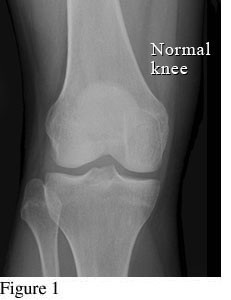

Hình ảnh so sánh giữa khớp bình thường và khớp bị thoái hóa khớp gối

Để phân biệt các giai đoạn của bệnh thoái hóa khớp gối, cần dựa vào phim X- quang theo tiêu chuẩn chẩn đoán thoái hoá khớp của Kellgren và Lawrence như sau:

Hình ảnh khớp gối trên phim X-quang: Khe khớp gần như bình thường, có thể có gai xương nhỏ.

Hình ảnh của khớp gối trên phim X-quang: Khe khớp hẹp nhẹ, có gai xương nhỏ.

Hình ảnh của khớp gối trên phim X-quang: Khe khớp hẹp rõ, nhiều gai xương kích thước vừa, đặc xương dưới sụn, đầu xương có thể bị biến dạng.

Hình ảnh của khớp gối trên phim X-quang: Khe khớp hẹp nhiều, gai xương có kích thước lớn, đặc xương dưới sụn, đầu xương biến dạng rõ.